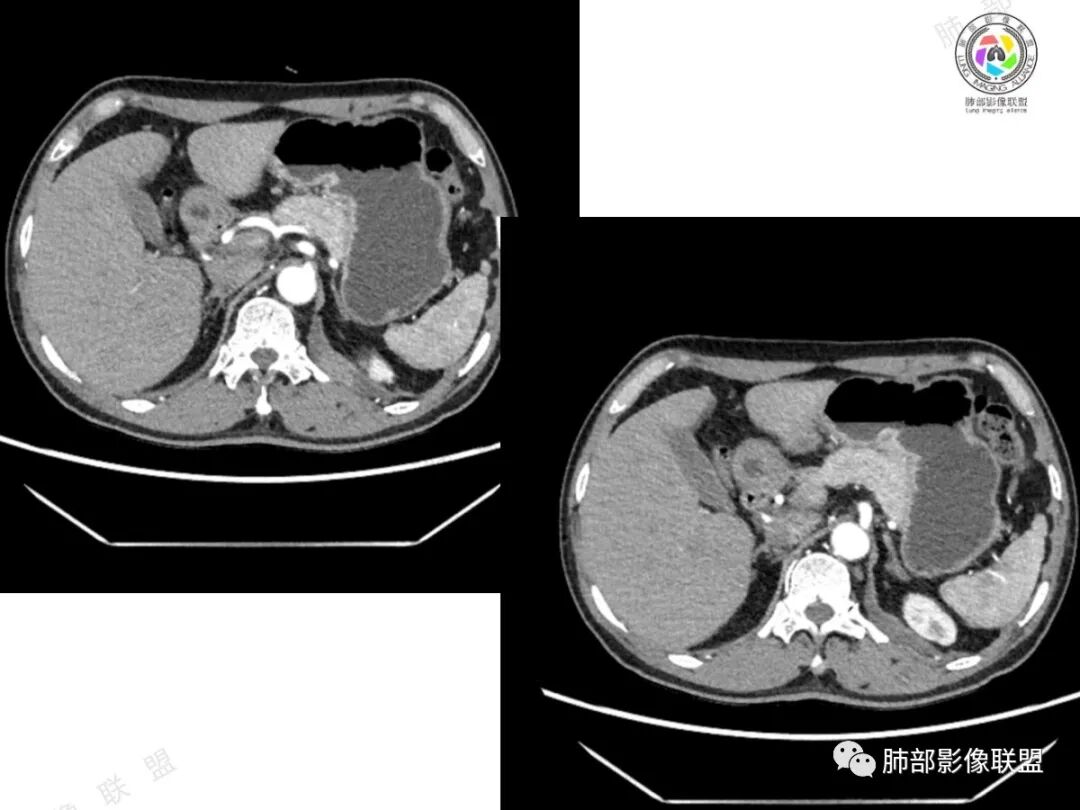

2、影像所见:左侧纵隔紧贴心包铸型生长巨大混杂密度肿块,边界清楚,临近结构受推挤移位,无明显外侵征象。肿块自主动脉弓旁一直顺延到至膈顶,呈“垂乳征”。病灶脂肪成分居多,斑片状、结节状及团块状实性密度成分散落其中,呈地图样分布,实性成分偶见低密度线样分隔,未见明确钙化影。增强扫描实性成分呈延迟明显强化,并见强化血管影。纵隔内有肿大淋巴结,未见胸腔积液,肺内及胸膜未见转移性病灶。

③畸胎瘤:多见于年轻患者,除实体部分的软组织密度、液体部分的水样密度和脂肪组织的脂肪密度外,钙化和骨化较常见,特征性表现是可出现脂肪-液体平面,有时在此界面出现线状及条索状混杂密度影为毛发团。成熟囊性畸胎瘤由分化成熟的组织构成,可以只有脂肪和囊变或者只有囊变。本例年龄较大,未见明确钙化及骨化,畸胎瘤似乎缺乏影像学证据。

④胸腺瘤:常见于40岁以上患者,是最常见的前纵隔肿瘤,大多数位于前纵隔,其次为心包旁,常偏侧生长,多数密度均匀,大于15㎝罕见,一般轻-中度强化,少数可明显强化。黄勇老师认为,胸腺瘤病理标本上均伴有不同程度间隔存在,随着侵袭性增强,分隔会逐渐不显著。当病灶有明确分隔,较均匀强化时,胸腺瘤一定要考虑到。